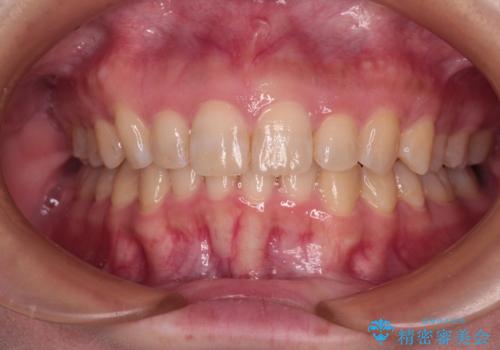

【出っ歯(飛び出した前歯)・がたつきでお悩みの方必見】インビザライン矯正の症例

![[ 出っ歯を治したい ] マウスピース矯正での上顎前突治療の症例 治療前](https://seimitsushinbi.jp/wp/wp-content/uploads/2022/03/IMG_9997-3-500x350.jpg?v=1648378247)

![[ 出っ歯を治したい ] マウスピース矯正での上顎前突治療の症例 治療後](https://seimitsushinbi.jp/wp/wp-content/uploads/2022/03/IMG_6262-500x350.jpg?v=1648378353)